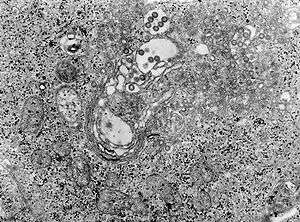

TEM micrograph of tissue infected with Rift Valley fever virus